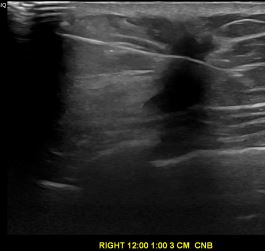

상기환자는 만져지는 멍울로  내원하신 40대

여성분으로 의심스러운 우측혹 조직검사 시행해 침윤성암 으로 진단되었습니다